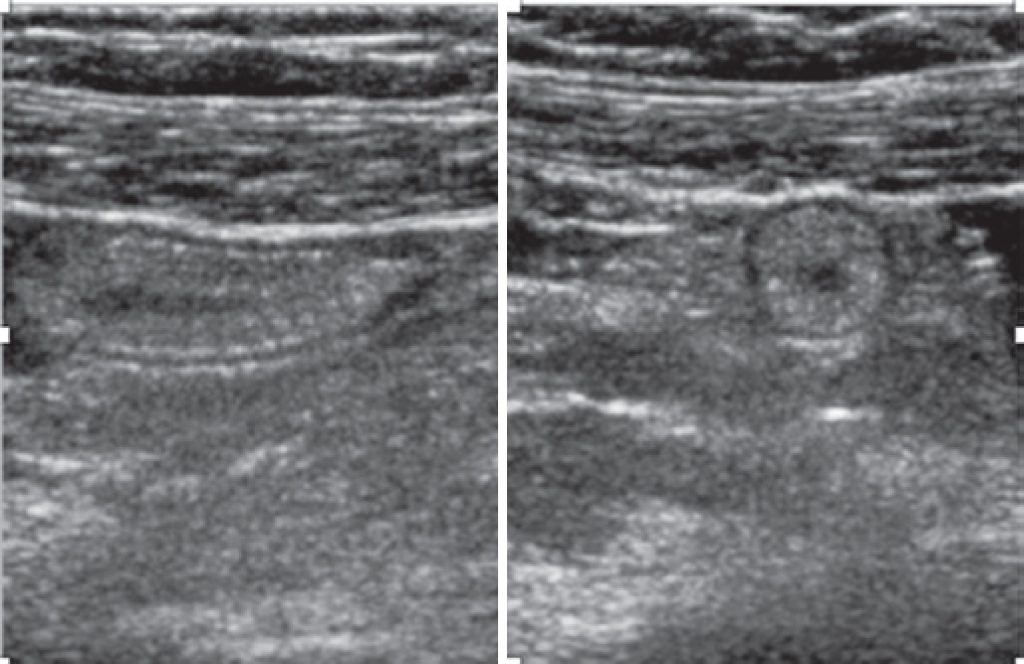

Paciente de 34 anos, do sexo feminino, grávida, chega ao pronto-socorro com queixa de dor na fossa ilíaca direita piorando nos últimos 2 dias com suspeita de apendicite aguda. Foram solicitados exames laboratoriais, que estavam dentro dos limites de normalidade para aspectos infecciosos e inflamatórios. Exame de imagem também foi solicitado, sendo a ultrassonografia o método de escolha, que revelou gravidez em curso sem alterações e espessura da parede do apêndice sem sinais inflamatórios. Ainda com suspeita de apendicite aguda, foi realizada ressonância magnética, confirmando a hipótese de lipomatose do apêndice cecal.